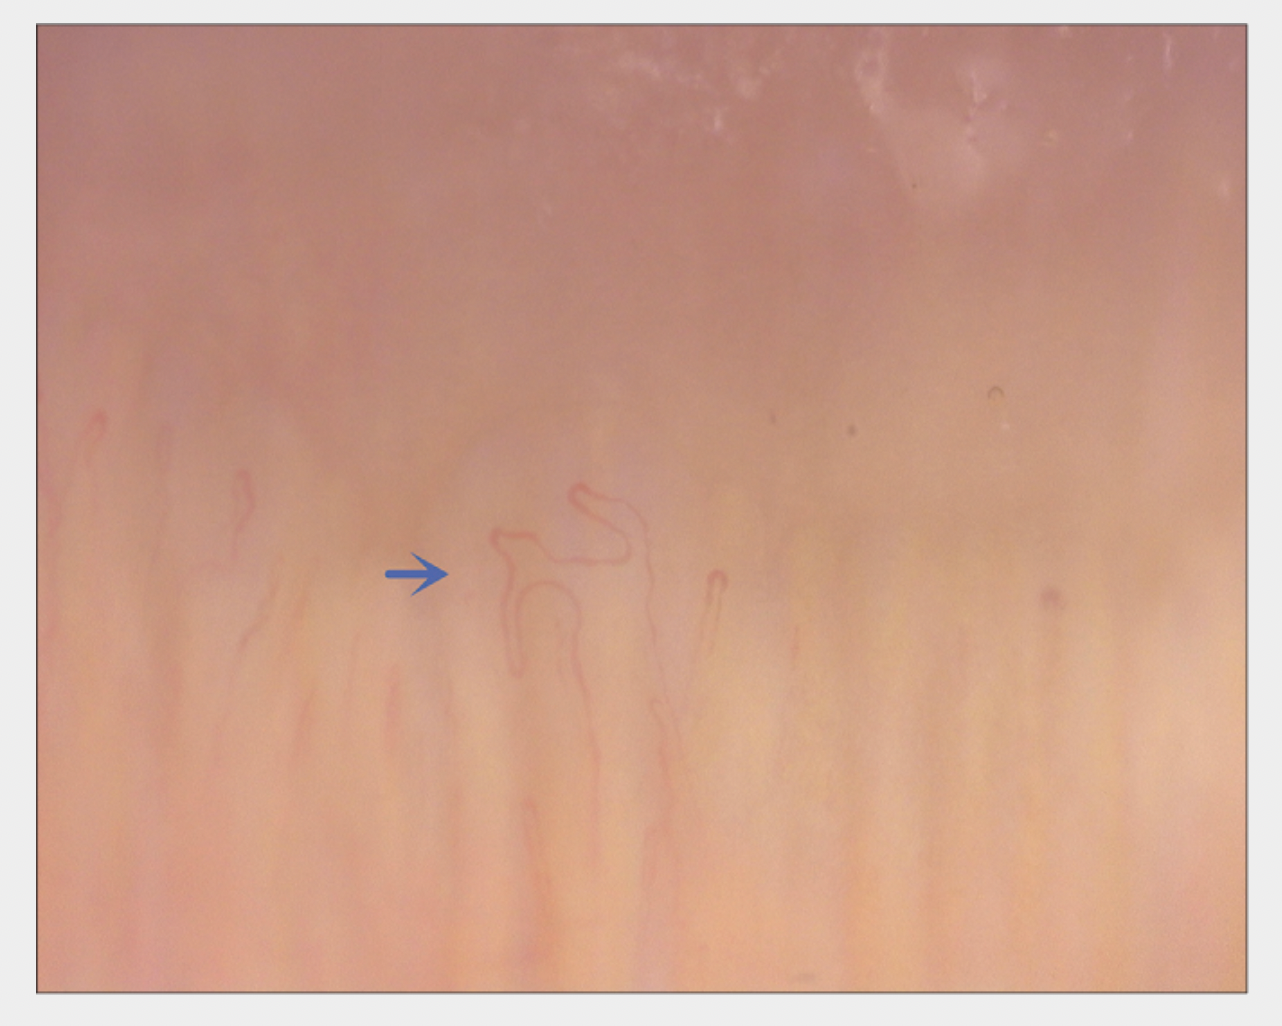

BIZARRE CAPILLARIES

Bizarre capillaries are More Common in Nail Capillaries from Patients with Androgenetic Alopecia Compared to Controls. Source: Cao L et al. Nailfold capillaroscopy alterations in androgenetic alopecia: A cross-sectional study. Indian J Dermatol Venereol Leprol. 2022 Feb 28;1-7. Image shown with creative commons license.

DILATED CAPILLARIES

Dilated capillary areas are More Common in Nail Capillaries from Patients with Androgenetic Alopecia Compared to Controls. Source: Cao L et al. Nailfold capillaroscopy alterations in androgenetic alopecia: A cross-sectional study. Indian J Dermatol Venereol Leprol. 2022 Feb 28;1-7. Image shown with creative commons license.